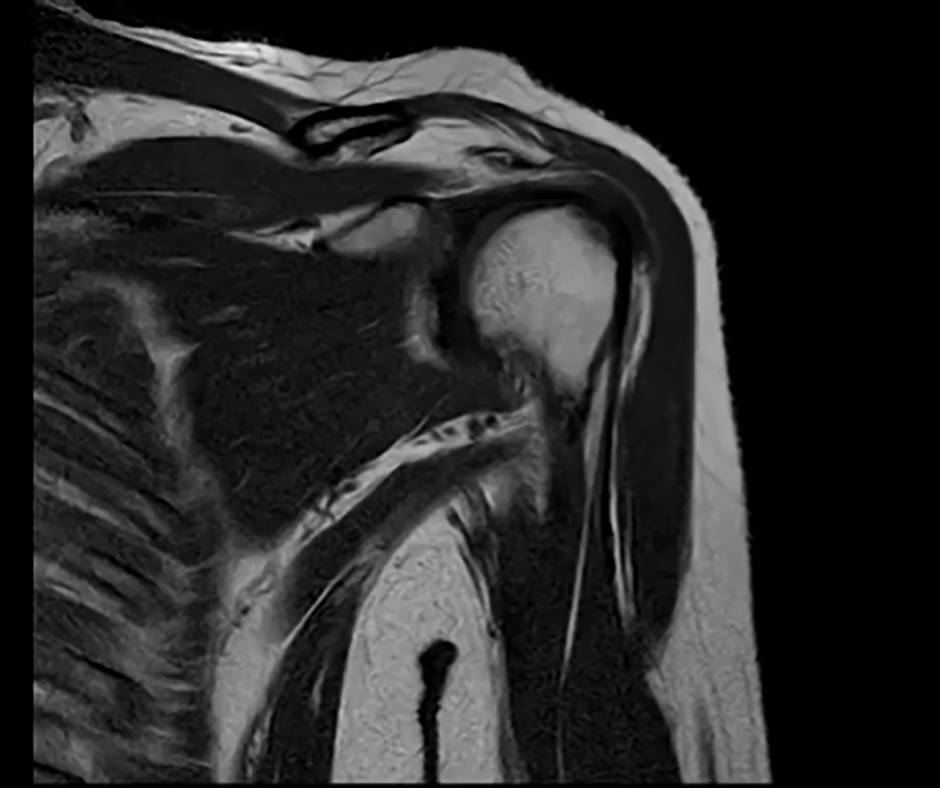

Could an AI-Powered Enhancement of MRI be a Pre-Op Game Changer for Total Shoulder Arthroplasty?